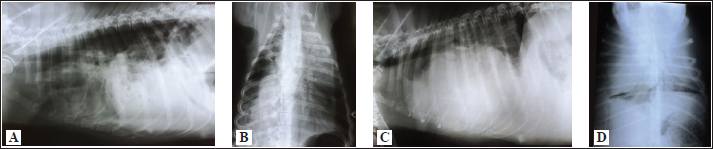

Fig. 2. A and B. Measurements of blood vessels relevant to the HWD in LL (A) and DV (B) radiographs: RCrLA – the width (mm) of the RCrLA, VCC – the width (mm) of the VCC, Ao – the width (mm) of the Ao, T4 – the length (mm) of the body and caudal disc of the T4 vertebra, 4.r – the width (mm) of the 4.r, RCaLA – the width (mm) of the right caudal lobar artery, 9.r – the width (mm) of the ninth rib. Ethical approvalAccording to the national law, an ethical approval for this research was not needed. However, a written consent was obtained from the owners. This study was carried out in compliance with the existing animal welfare laws in Europe. Statistical analysesA commercial software package TIBCO Statistica was used for the following statistical analyses: descriptive statistics, the correlation coefficient (r) and coefficient of determination (R2), the Fisher probability test, and the Wilcoxon matched pairs test. The prevalence of subjective radiographic parameters was expressed in absolute and relative numbers (percentages). The correlations between skeletal units (T4, M, S4, TI), as well as between LA, SA, the sum of LA and SA with skeletal units of heart size, were assessed. The correlation was classified as negligible (r=0.00–0.09), weak (r=0.10–0.39), moderate (r=0.40–0.69), strong (r=0.70–0.89), and very strong (r=0.90–1.00). In order to assess the occurrence of subjective parameters of cardiomegaly and abnormal lung patterns in the dogs with HWD before and after therapy the Fisher probability test was used. The Fisher probability test was followed by the post hoc false discovery rate (FDR) test (Benjamini and Hockberg, 1995). The objective parameters of radiographic assessments (cardiac size and shape, and blood vessels measurements) were expressed as the mean ± SD, as well as the minimum and the maximum. The same parameters in the dogs with HWD before and after therapy were assessed by using the Wilcoxon matched pairs test. A probability value of p < 0.05 was considered as significant. ResultsIn 2 out of 40 dogs (2/40 dogs or 5% of dogs), radiographs could only be assessed subjectively. These two dogs had the most severe radiographic features in the areas of lung fields, which made it impossible to assess their cardiac silhouette and vascular pattern, either subjectively or objectively (Fig. 3A–D).

Fig. 3. Radiographs of two dogs with the most severe changes. 3A and B - LL and DV views of a 9-year-old female Rottweiler. Massive opacities can be seen in the ventral areas of the cranial, middle and accessory lobes (in LL view), and in the left cranial, right cranial and caudal and accessory lobes (in DV view). These changes cover the heart silhouette. Also, reduced flows to the left caudal and right middle lobes can be seen. In the caudal lobes in LL view, and in the right caudal lobes in DV view, air alveolograms can be seen. 3C and D - LL and DV views of a 5-year-old female mix-breed dog: Massive opacification in the ventral areas of lung lobes in LL view made it impossible to define the heart silhouette. The trachea lies almost parallel to the spine, with a mixed interstitial-alveolar pattern of the caudal lung lobes. On the DV view diffuse opacities in lung lobes prevent cardiac silhouette and vascular pattern assessment. The radiographs of all other dogs were considered suitable for assessment both subjectively and objectively. Aside from 4 dogs, in which only LL were available, there were also two dogs in which opacity in their lung field in their DV radiographs enabled only the assessment of some subjective and objective parameters. The most prevalent features of subjective radiographic assessment (Table 3) of the HWD in these dogs were the increased sternal contact (91.89%), the rounding of the right cardiac border (89.65%), and the RCaLA larger than the vein (86.67%). Radiographs of almost all the dogs (37/38 dogs or 97.37%) or all of them (38/38 dogs or 100%) were eligible for assessment and detection of the more prevalent parameters of cardiomegaly (increased sternal contact, rounding of the cranial heart border) and abnormal lung field (loss of margination of pulmonary vessels). However, not each of the subjective assessment parameters could be analyzed in all the dogs. In 55.88% of the dogs (19/34 dogs), it was not possible to compare the width of the RCaLA and the corresponding vein. The most common reasons were one or several of these: unclear vein margins, opacity of the surrounding lung field, incorrect dog position. In 55.26% of the dogs (21/38 dogs), it was not possible to define whether the VCC is larger than the Ao due to the dogs’ respiratory cycle (position of the diaphragm) at the time of radiographic recordings, the opacity of surrounding tissues and not clearly visible margins of the Ao. In one dog (5.88% of dogs), VCC was wider than the Ao. Table 3. Prevalence and feasibility of subjective radiographic features in the dogs with HWD.